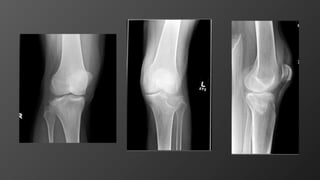

Knee Dislocation

• Mechanism

• High-energy trauma

• 3 out of 4 ligaments should be torn to dislocate the knee

• Imaging

• X-Ray: AP, Lateral

• MRI for surgical planning (later)